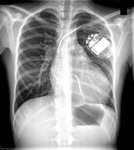

Hypertrophic cardiomyopathy

CXR of a patient with HCM demonstrating cardiomegaly

From the collection of Melanie Everitt MD, Heart Failure & Transplantation Program, Primary Children's Medical Center, Salt Lake City, UT; used with permission